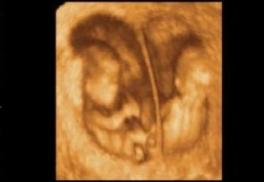

Hallazgo hecho en gemelos: fetos de apenas 18 semanas ya socializan